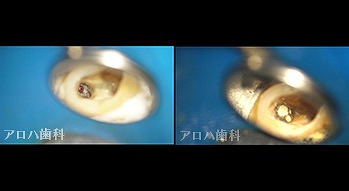

case4

再根管治療 2年予後

破折器具除去もあり

再根管治療の汚染の改善